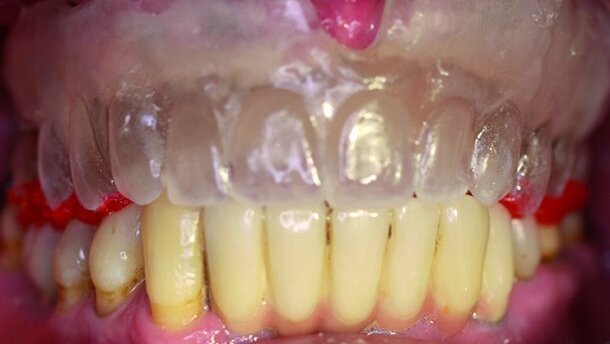

L’extraction de plusieurs dents résiduelles qui ne pouvaient être restaurées, et la pose de six implants aux positions 15, 14, 13, 23, 24 et 25, ont été suivies par la réalisation d’une prothèse complète amovible. Sa fonction et son esthétique ont ensuite été optimisées, après la cicatrisation des lésions dues à l’extraction et la disparition des ulcérations d’origine prothétique. Le cas échéant, l’angulation, la forme et la couleur des dents artificielles, ainsi que la forme de l’appui muqueux de la prothèse, ont aussi été rectifiées (Fig. 1a). La prothèse résultante a été portée par le patient jusqu’à la restauration définitive de son maxillaire, prévue sous forme d’une prothèse amovible supra-implantaire pourvue de couronnes télescopes comme ancrages.

Les implants ont été désenfouis et la prothèse a été modifiée en vue d’obtenir un espace suffisant pour les piliers de cicatrisation. Une réplique de la prothèse a été fabriquée dans une résine transparente (Paladur, Heraeus, Hanau, Allemagne, Fig. 1b). Elle a fait l’objet d’une essayage et les contraintes occlusales mineures ont été rectifiées (Fig. 1c). Des occlusogrammes ont été élaborés en occlusion centrée, au moyen d’une résine de modelage (Pattern Resin®, GC, Al-sip, Illinois, États- Unis ; Fig. 1c) et des moulages de la prothèse originale. Ensuite, la réplique prothétique a été montée sur un articulateur et l’occlusion a été vérifiée (Fig. 2a) à l’aide des occlusogrammes. Le système de transfert utilisé pour l’empreinte à ciel ouvert, était constitué de tenons en titane et de chapes en plastique (Dentegris, Duisburg, Allemagne, Fig. 2b). La réplique prothétique a été soigneusement modifiée par la création d’ouvertures internes dans la zone des implants, de façon à pouvoir l’utiliser comme porte-empreinte individuel. Ceci permettait également de positionner parfaitement la réplique après la mise en place des tenons pour empreintes. Les empreintes ont été réalisées dans un matériau en polyéther (Impregum, 3M ESPE, St. Paul, Minnesota, États-Unis). Pendant cette procédure, la réplique prothétique a été maintenue en occlusion centrée, au moyen des occlusogrammes (Fig. 3a).